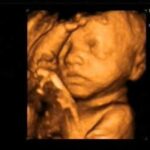

El ultrasonido 4D permite observar los rasgos y movimientos del bebé con gran claridad.

Además de lo emocional, tiene un rol clínico importante: ayuda a evaluar el bienestar fetal, detectar malformaciones y monitorear el desarrollo del embarazo.